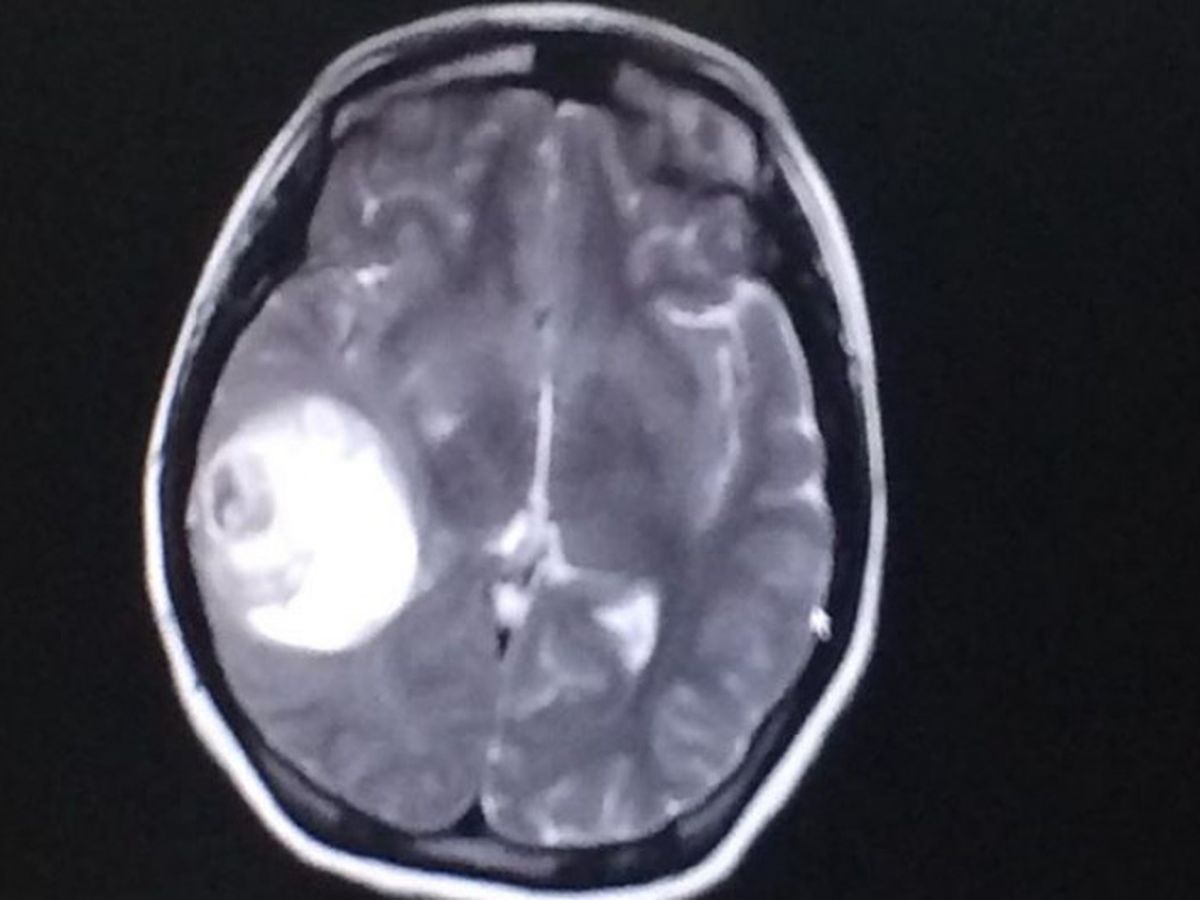

I have suffered from chronic migraines for years. This past Wednesday, I had a seizure at work where it was discovered that I had been living with a 5cm brain tumor. I had a craniotomy Friday, December 29th and was discharged from the hospital Sunday, December 31st (New Year's Eve!) Even though this was not how I had imagined ringing in The New Year, I feel like the luckiest person in the world. I'm thankful to have had my seizure in a safe environment with friends and coworkers around me, rather than on my walk home alone from the train that night. The nuerosurgeon said I should be in recovery for 6 weeks and I am determined to remain hopeful and positive while I recover. Within that time, I am hoping to raise $10,000 in order to help with my medical bills and cost of living expenses. Any donation is greatly appreciated; thank you!